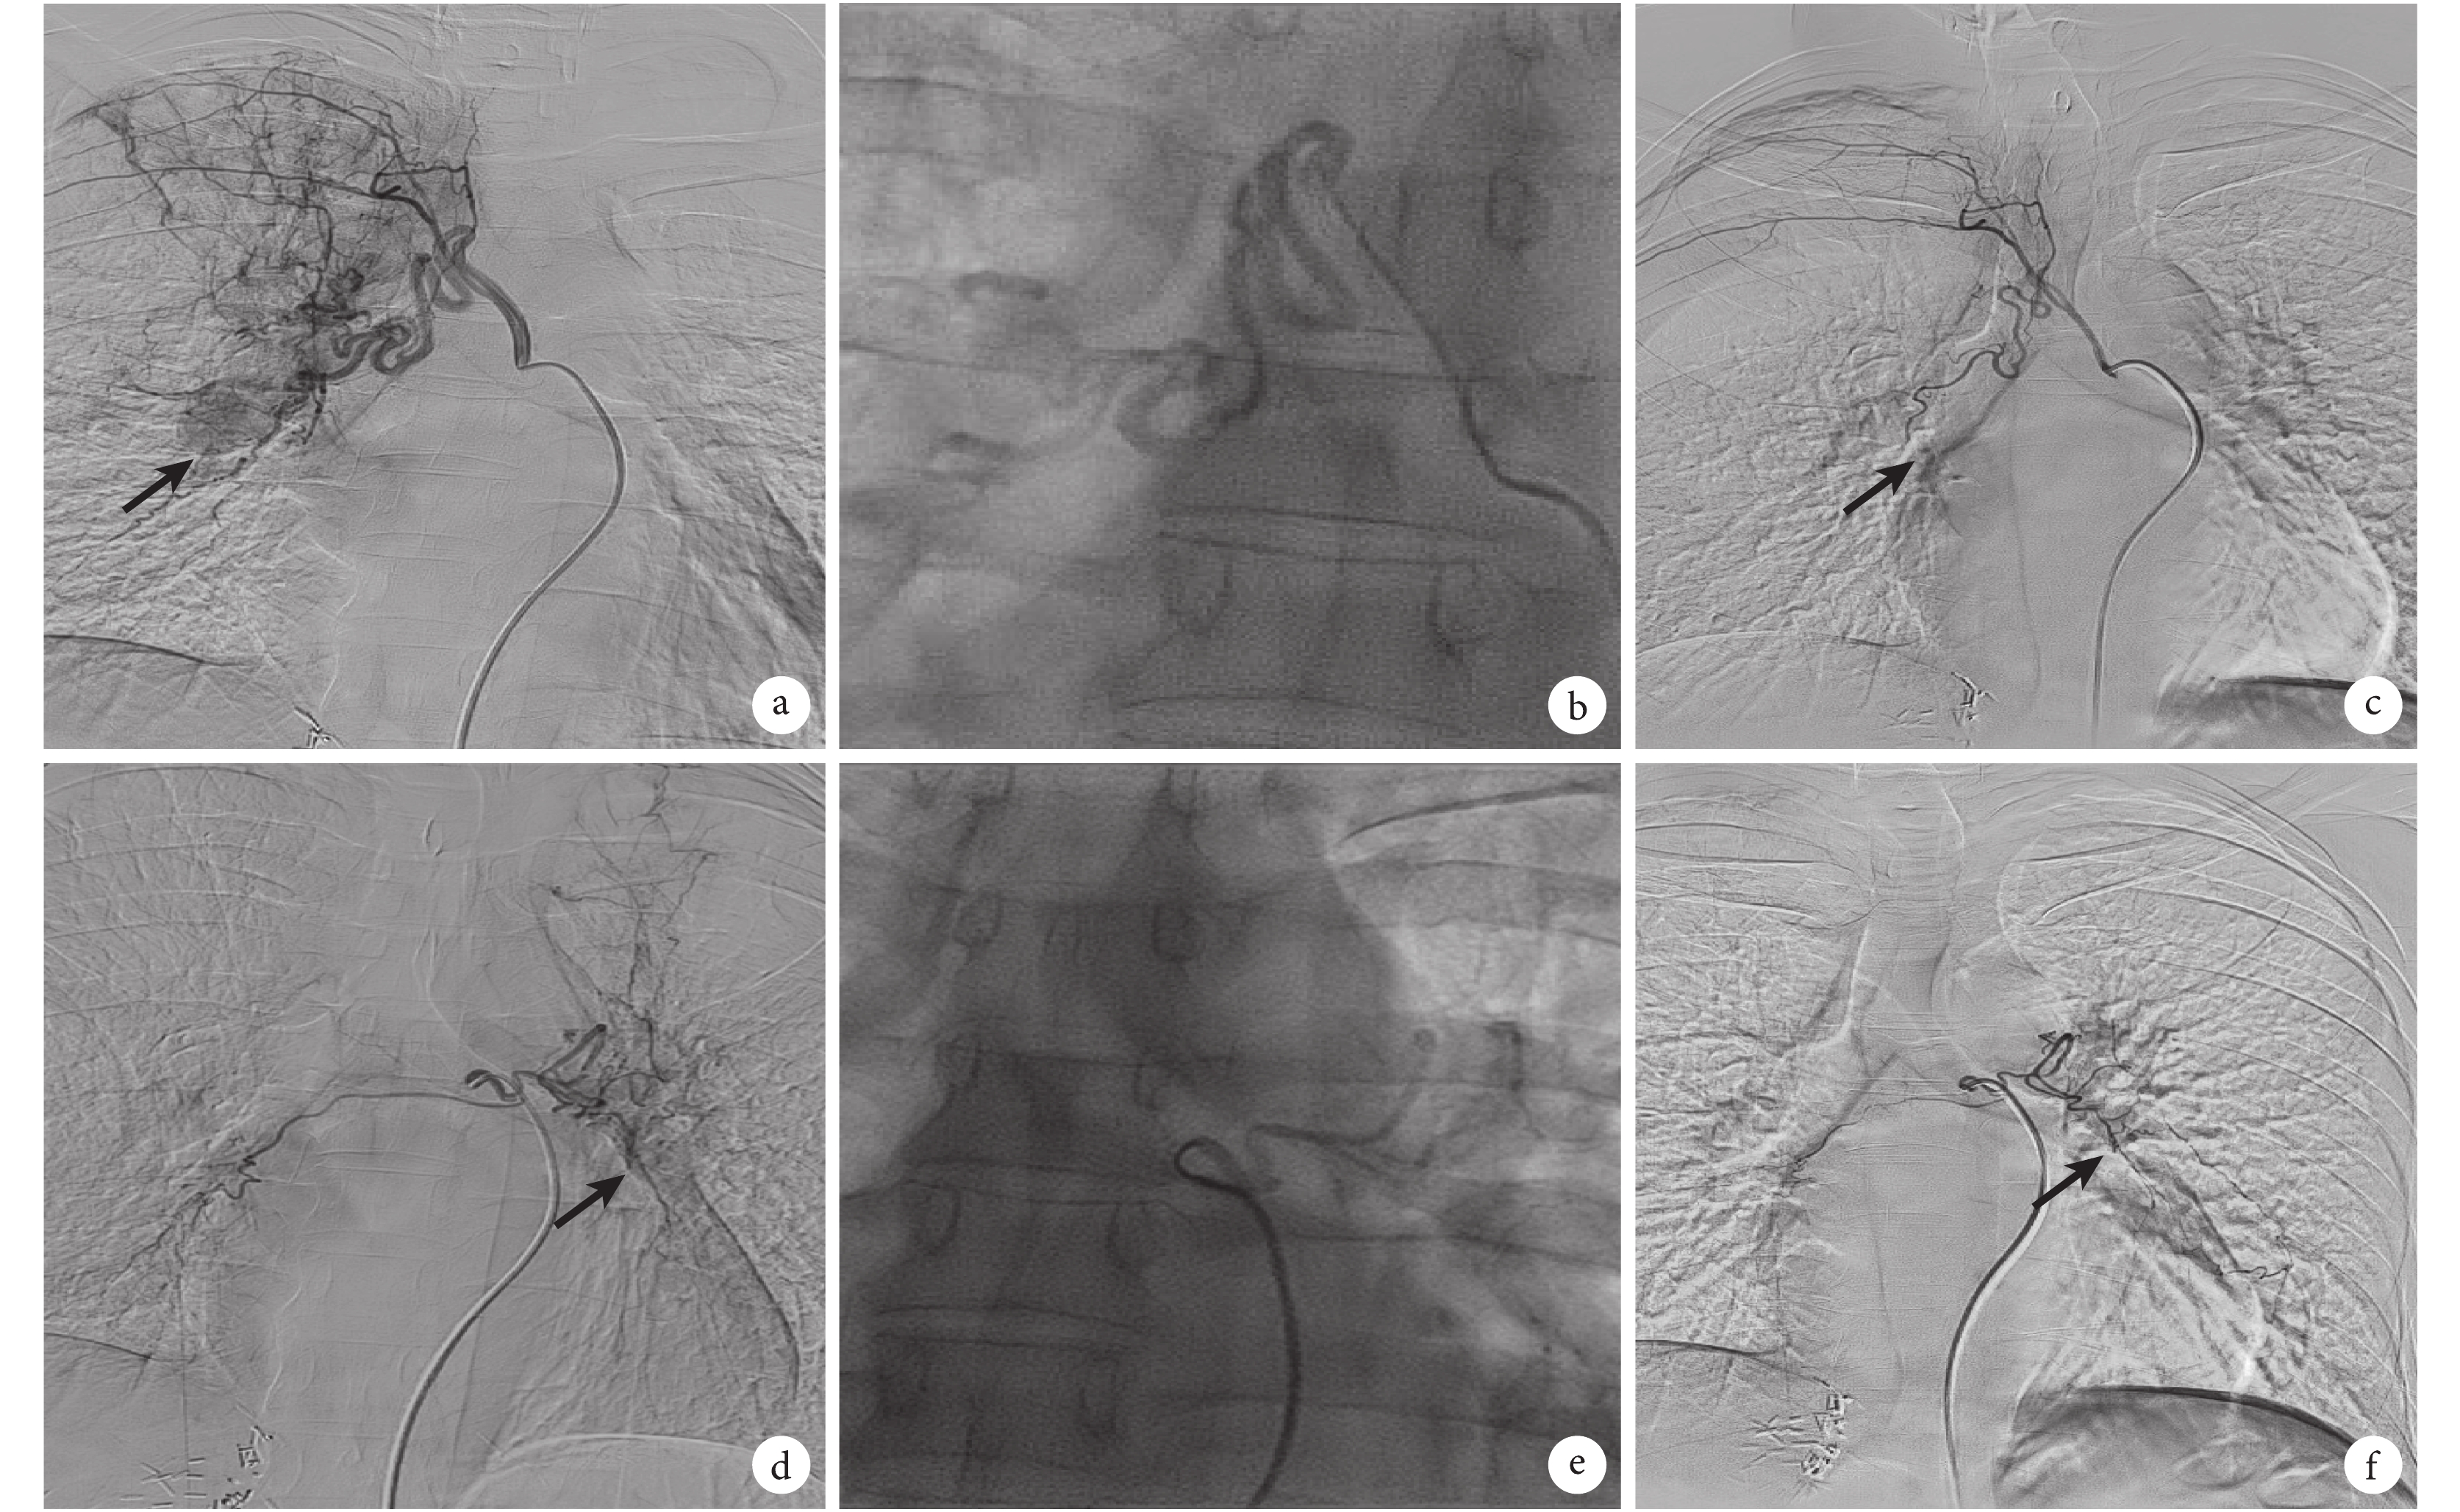

a、b. 術前雙側內乳動脈造影,可見肺門縱隔淋巴結腫瘤染色;c. 患者術前行肝動脈造影,可見多個團狀腫瘤濃染區域(黑箭);d、e. 術后 2 個月行雙側內乳動脈造影,可見腫瘤染色明顯減少,變淡;f. 術后 2 個月再行肝動脈造影,可見肝臟腫瘤濃染團塊明顯減少,部分消失(黑箭)